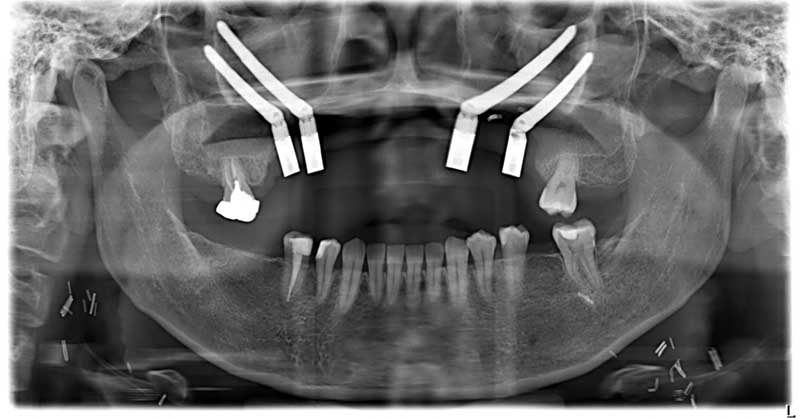

一位40歲的口腔癌患者許小姐,於2024年至中山醫學大學附設醫院口腔顎面外科就醫,該名患者罹患上顎牙齦癌,需手術切除大範圍上顎骨,不僅影響外觀,口內鄰近腫瘤的10顆牙齒亦需一併切除。術前運用電腦數位模擬技術,精準規劃腫瘤切除範圍及術後牙齒重建位置,並模擬將植體植入顴骨中,以彌補上顎骨缺損。手術當日,由中山附醫口腔顎面外科邱昱瑋主治醫師、陳怡孜主治醫師及陳珮吟主治醫師組成的醫療團隊主導,採用電腦數位模擬手術,先模擬腫瘤切除範圍,再模擬出切除後牙齒該有的排列位置,另外,關於上顎骨先前已被部分切除,透過電腦模擬將植體植入顴骨當中;手術當下,結合切割導版與電腦導航系統輔助,所有相關手術程序於同一日一次完成,精準完成上顎口腔癌腫瘤切除、頸部淋巴清除、顴骨植牙及游離皮瓣重建,大幅縮短治療時程,降低患者身體負擔,目前患者許小姐已成功恢復正常咀嚼功能,生活品質大幅提升。